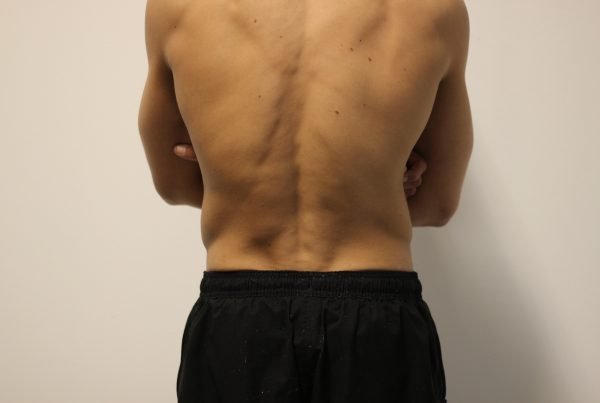

Lage rugklachten

Lage rugklachten

Lage rugklachten vormen een veelvoorkomend gezondheidsprobleem dat mensen van alle leeftijden en achtergronden treft. Deze…